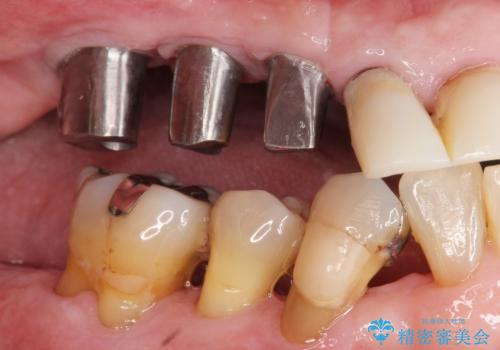

- 歯がぐらぐらで咬めないことを主訴に来院された患者様です。

他院では上顎骨が薄いためインプラントできないと言われたとのことでした。

精査したところ、歯周病に罹患した歯を長年放置したことから骨吸収が進行し、上顎骨の厚みはとても薄くなっていました。

全顎的な歯周病治療を行ったのち、上顎洞底挙上術(上顎骨に骨を増やす手術)を併用したインプラント埋入を行いました。